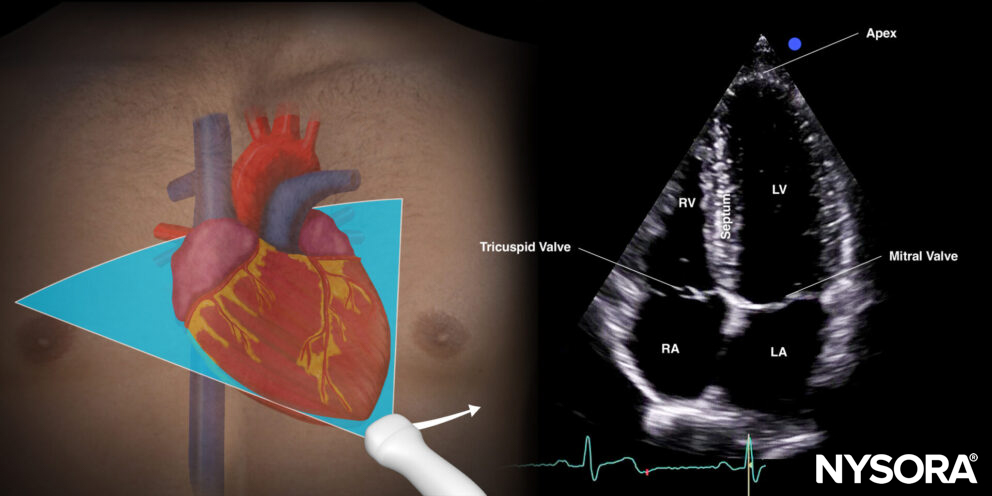

Apical four-chamber view (A4C): tricuspid, mitral, and aortic valves

Transducer position and sonoanatomy of the apical four-chamber view.